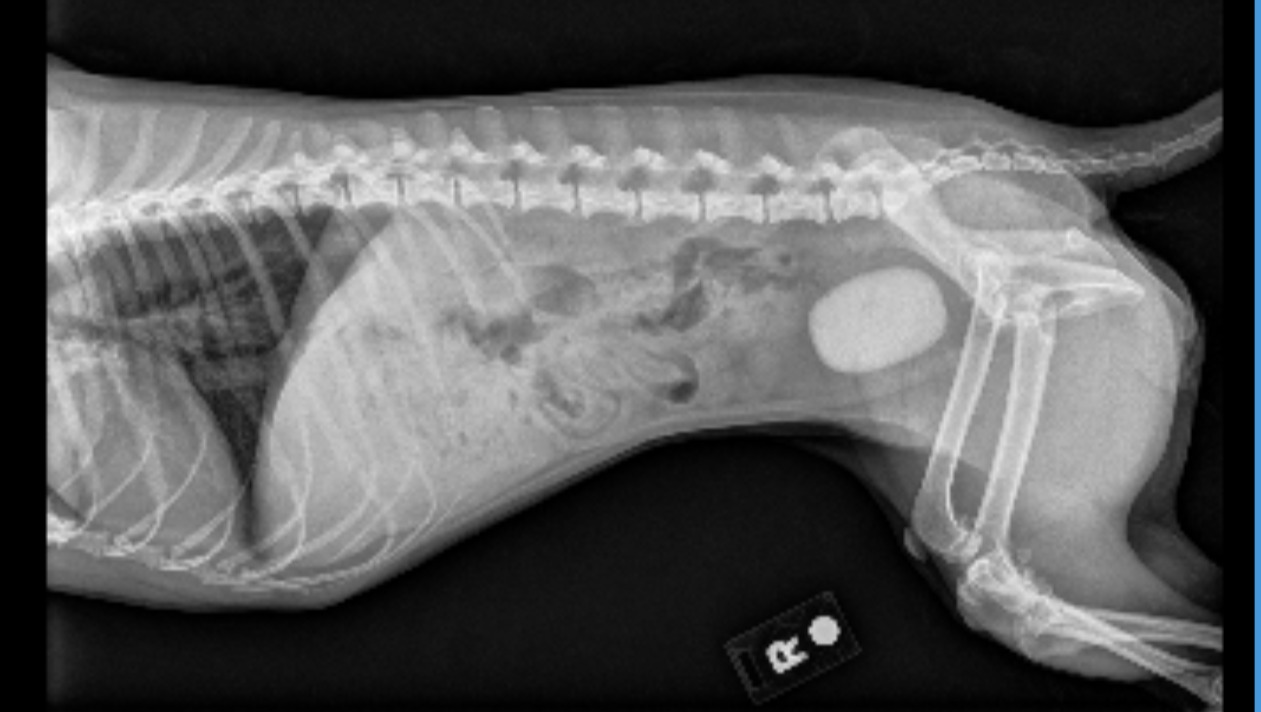

Hello, I'm Antonio, Moca's owner. Moca is about 8 years old now and is going through issues with a large bladder stone that requires a surgery that costs about $3500. Unfortunately, as an 18 year old college student, it is difficult to pay for this surgery alone. I currently work a part time job to help with school tuition and I simply can't afford this operation. Anything is greatly appreciated and would help immensely. Thank you for your support